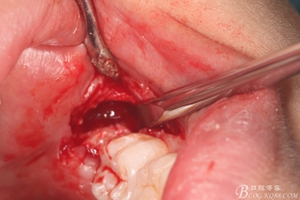

圖15.牙冠完全取出后,用微創(chuàng)丫挺取根

圖16. 38的牙根完整取出,對下頜神經(jīng)管未施加壓力